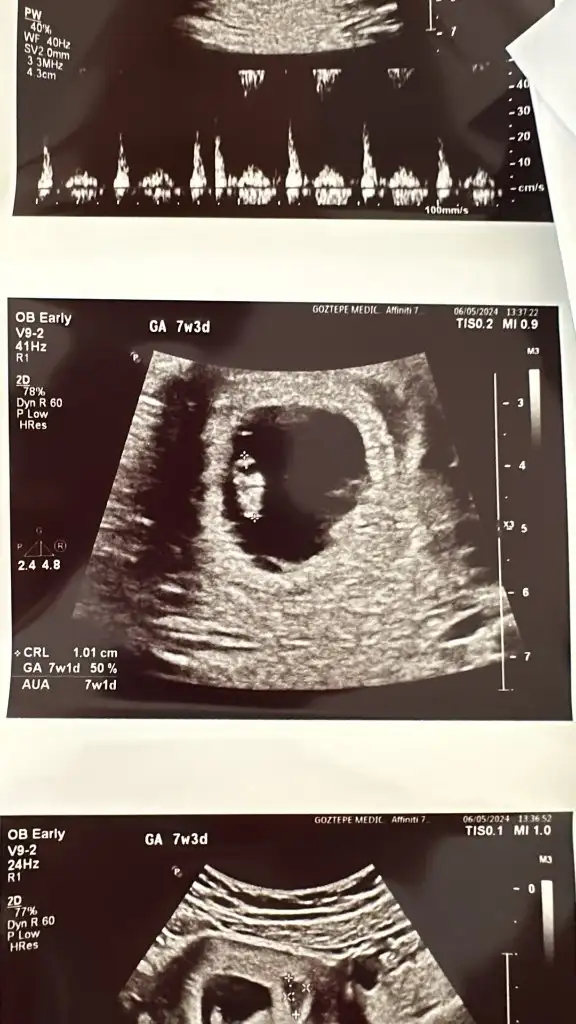

yokum henüz ultrasona girmedim diye bilgi vermemiştim. kesinleşsin ondan sonra gireceğim listeye ben de :) Şimdilik elimde sadece mide bulantım ve bas donmem var bir de pozitif gebelik testimSanırım daha önce de sormuştum bu soruyu çünkü İrlanda cevabını aldığımı hatırlıyorum ama siz miydiniz emin değilim. Tabloda var mısınız??